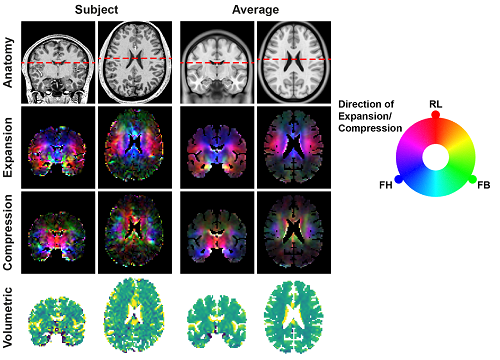

Caption:

This image shows the deformation of brain tissue in healthy volunteers. The first two columns of images represent one individual subject. The third and fourth columns of images show the average result across 9 volunteers, making the images look smoother (with less noise). The first row shows the anatomy of the brain for reference. The second and third rows show tissue expansion and concurrent tissue compression. Here the intensity indicates the magnitude of the expansion/compression and the colors show the direction: red is right-left (RL), green front-back (FB) and blue is the direction feet-head (FH). The net increase (yellow) or decrease (blue) in tissue volume is shown in the bottom row. The images of tissue expansion (second row) nicely show how the tissue in healthy individuals stretches toward the center of the brain.